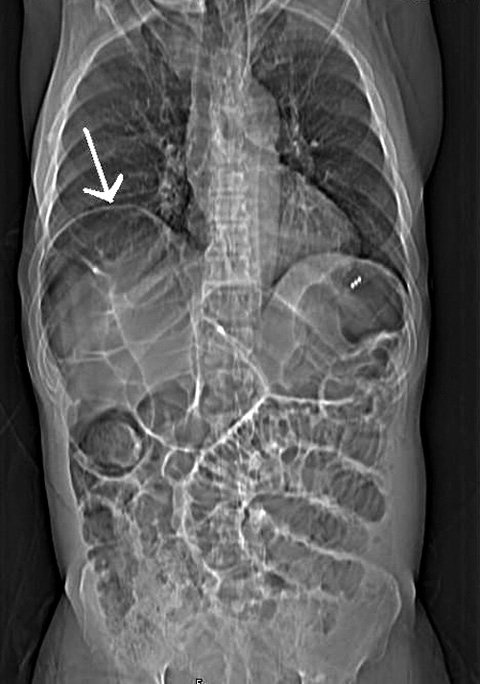

A chest x-ray revealed hepatodiaphragmatic interposition of the large bowel (Chilaiditi sign). Abdominal computed tomography confirmed the presence of bowel loops anterior to the liver (Figures, arrows) and grossly dilated large bowel with no evidence of pneumoperitoneum. Biochemical analysis revealed hyponatraemia and hypokalaemia.